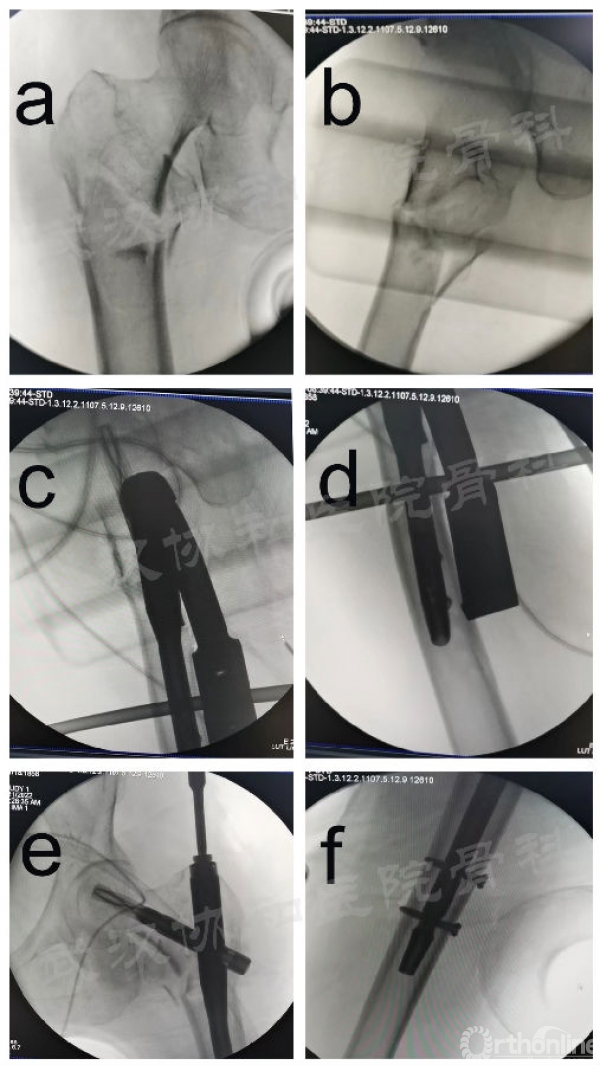

术中透视图。DRTR复位后股骨转子间骨折前后位(a)和外侧位(b)影像学图;(c、d) 置钉后的侧位图;(e、f) 置钉后的前后位图

C臂X线透视引导下牵引复位并调整骨折断端位置,至骨折端复位。自大转子近端行纵向切口,长度为5-7cm。将主钉导针插入股骨大转子顶端,C臂X线检查确认导针已进入股骨髓腔,位置良好。开口扩打开髓腔,插入合适PFNA主钉,在透视位置下沿股骨颈方向钻入头钉导针。透视后,头钉导针正位位于股骨颈中下三分之一,侧卧位位于股骨颈中心,深度确定至股骨头软骨下骨位置。测量深度后沿头钉导针开口钻钻开皮质骨,置入适当的头钉,透视满意后锁定。然后借助导向器锁定远端锁钉。最后拧入主钉近端的尾帽并缝合伤口。